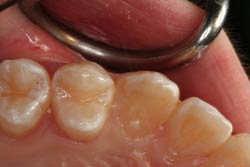

На очищенную жевательную поверхность зуба наносится герметик, который надёжно крепится к поверхности фиссуры. Благодаря своей высокой текучести, герметик проникает даже в очень узкие и глубокие фиссуры. Затем производится полимеризация герметика.

Цветовое отличие герметика от тканей зуба неслучайно, это делается для того, чтобы пациент мог самостоятельно контролировать целостность герметика. Процедура герметизации фиссур абсолютно безболезненна.